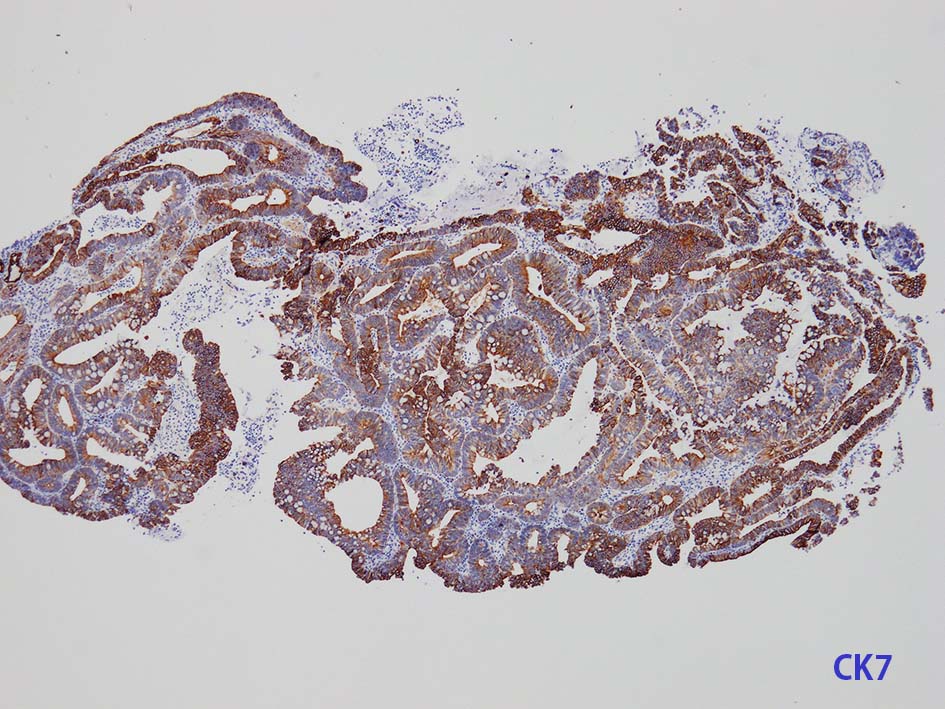

膀胱原発腺癌の診断に, サイトケラチン7および20、34βE12、トロンボモジュリン、CDX2およびβカテニンなどの免疫組織化学的パネルが提案されている。しかし他の原発部位に発生する腺癌と組織像だけでなく免疫組織化学的特徴が重複している. 原発性腺癌と転移性腺癌では予後や治療法が大きく異なるため, 鑑別診断において膀胱腺癌の診断を下す際には、臨床的、画像的、組織的、および免疫組織化学的な相関を注意深く確認する必要がある。

mark-g.gif 免疫染色